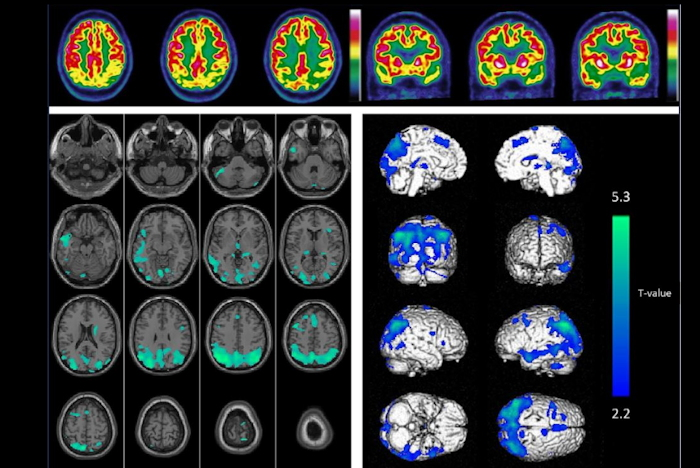

Tau protein neurofibrillary tangles and beta-amyloid plaque deposits are the two major pathological hallmarks of Alzheimer's disease, with tau PET and amyloid PET scans used to diagnose the disease. Research suggests that the accumulation of these proteins is a continuous process that starts decades before the onset of symptoms.